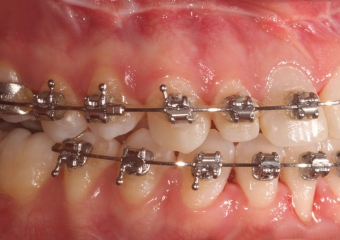

Mordida inicial - Clínica Cliniface

Mordida inicial